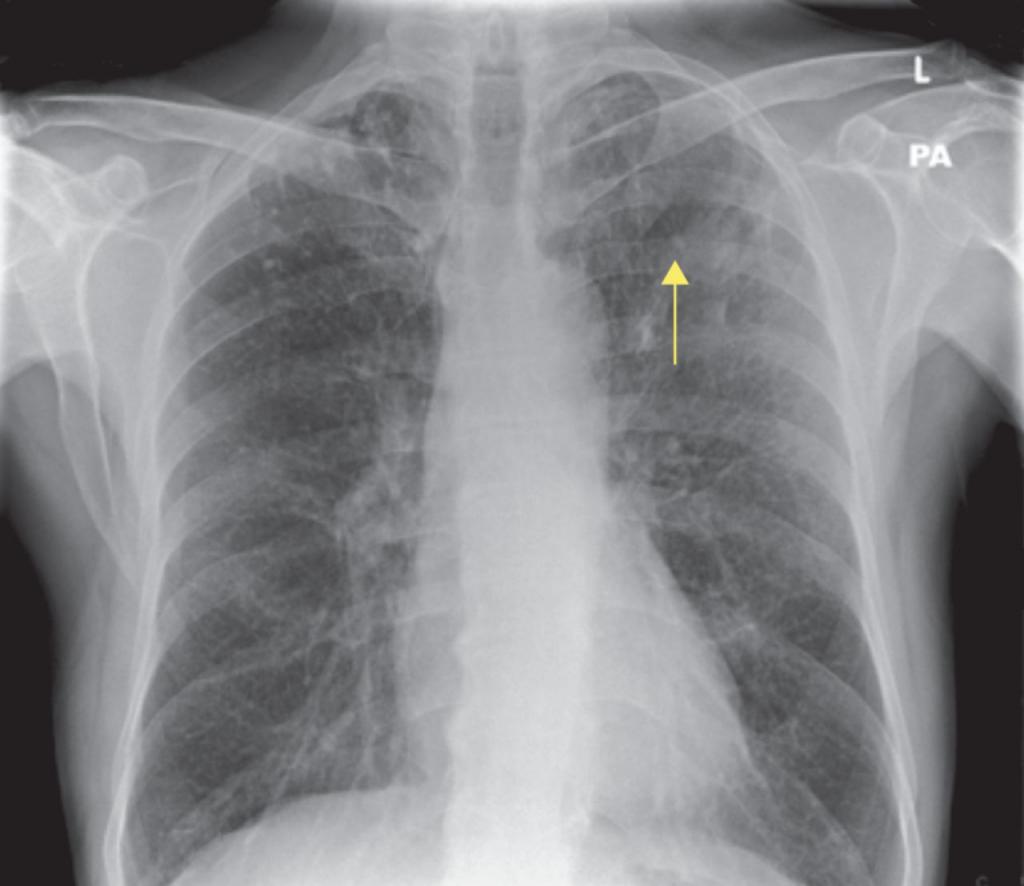

Рентген снимок атипичной пневмонии

Атипичная пневмония — собирательный термин, включающий инфекционно-воспалительные поражения тканей лёгких. Причинами являются нехарактерные возбудители — микоплазма, хламидия, легионелла, вирусы. Воспаление лёгких протекает с повышением температуры, одышкой, общим недомоганием.

Диагностировать патологический процесс можно при помощи рентгена. Так, для микоплазменной формы характерна неоднородная инфильтрация лёгочной ткани, она может определяться слабо или быть среднеинтенсивной.

При легионеллезной, на снимке видно уплотнения (инфильтраты) округлой формы, локализующиеся на поверхности одной доли лёгкого. В ряде случаев наблюдается слияние инфильтратов.

У 25% пациентов одновременно с пневмонией определяется плеврит, с незначительным скоплением секрета в плевральной полости.

Практически невозможно отличить пневмонию Legionella от других, основываясь на таком методе обследования. Присутствие легионеллы или хламидии подтверждается серологическим анализом крови.